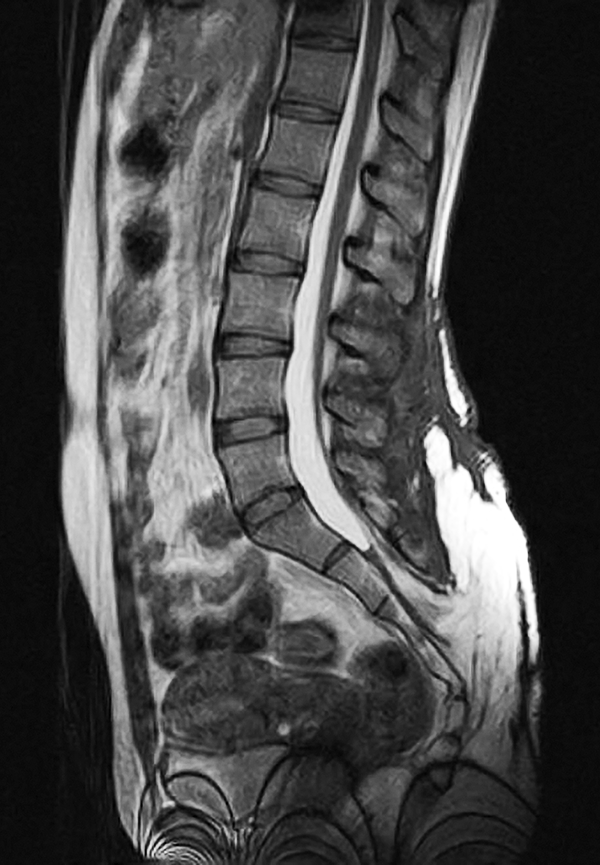

Presentamos un segundo paciente, perteneciente al grupo 2, de una paciente adulta joven, de 19 años, con antecedentes de una pequeña tumoración lumbar de aproximadamente 1.5 cm de diámetro que refiere tener desde el nacimiento (patología congénita). Refiere tener un crecimiento paulatino de dicha lesión hasta alcanzar un diámetro aproximado de 12 cm a los 18 años. Durante el siguiente año, la paciente consulta por presentar dicha tumoración de aproximadamente 25 cm de diámetro, la cual había aumentado de tamaño en asociación a un proceso infeccioso local secundario a un traumatismo leve en esa región (figs. 2 y 3). Se confirma el diagnóstico de un lipomeningocele y se le solicitan los estudios pertinentes. Se decide la intervención quirúrgica de la lesión, reparando el defecto mediante la exéresis de la pared del meningocele, con formación de un nuevo fondo de saco dural (figs. 4 y 5). La paciente evoluciona favorablemente, sin presentar síntomas de médula anclada al momento.

Figura 4: Imagen post-operatoria luego de la reparación del defecto espinal congénito.

Figura 5: Corte sagital de RM secuencia T2 del lipomeningocele: imagen postquirúrgica.